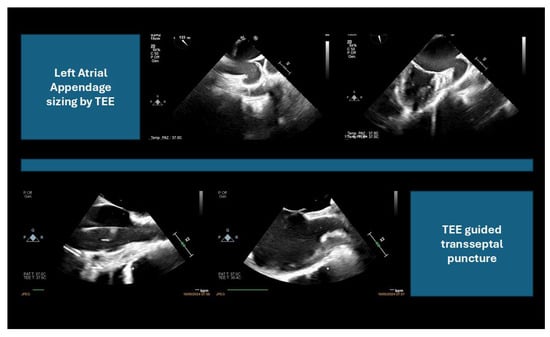

2.2. Intra-Procedural Imaging: Guidance During the Intervention